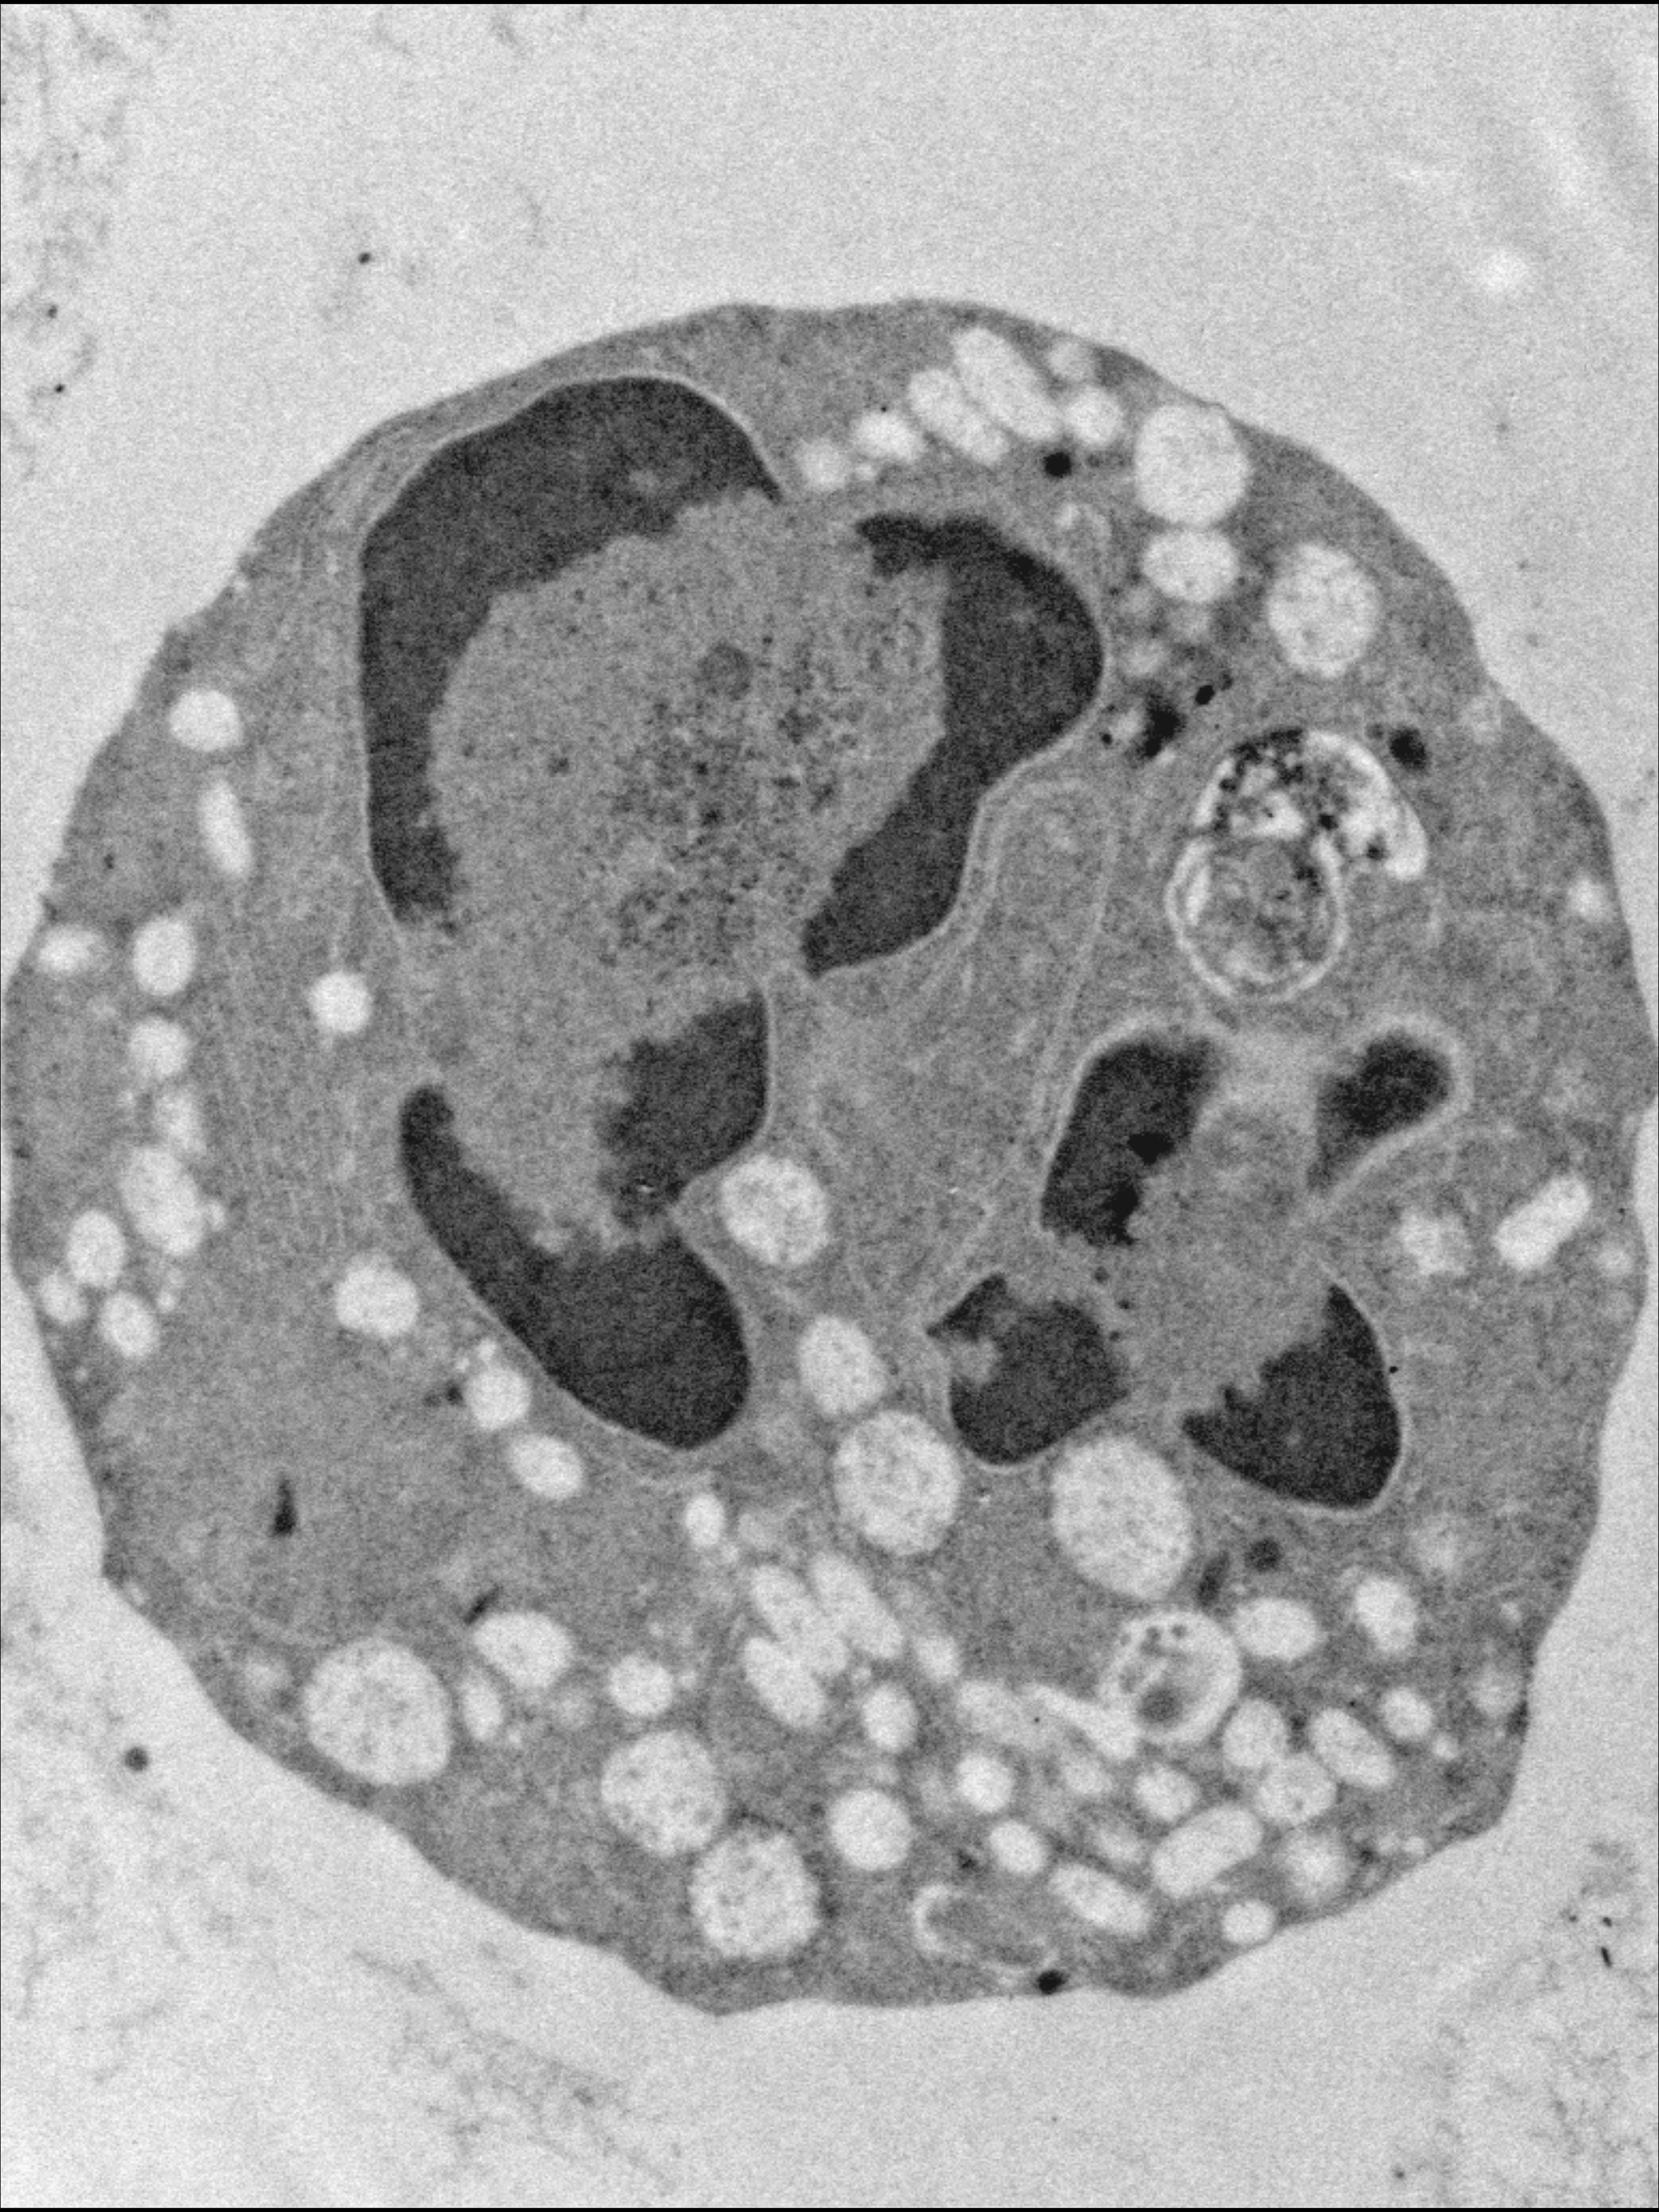

Analysis by transmission electron microscopy of the ultrastructural aspect of bone marrow cells in a patient with a heterozygous mutation in the SRP54 gene, which encodes the signal recognition particle 54 (SRP54) GTPase protein. Notice the preapoptotic neutrophil granulocytes with abnormal clumped chromatin and large cytoplasmic vacuoles. See the article by Bellanné-Chantelot et al on page 1318.